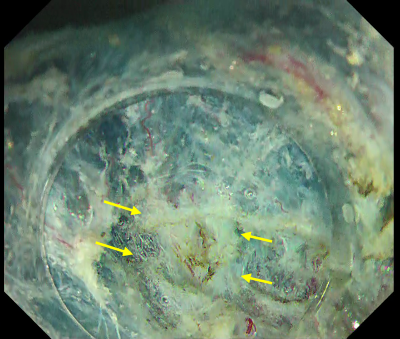

In this case, introduction into the submucosal layer appears more difficult than usual because the mucosa is thickened due to inflammation. We therefore applied the WPM². This technique was originally proposed for duodenal ESD but can be a powerful tool when introduction into the submucosal layer is difficult. As shown in Fig. 9, it effectively visualizes the tissue to be cut by properly using the tapered hood. Because immersion expands the visual field, the knob-shaped tip of DualKnife J can be precisely applied to the point to be cut, enabling truly precise ESD.

Once the DualKnife J has been introduced into the submucosal layer, you can use the PCM to excavate the central part and expose the fibrotic region (Fig. 9). After that, you can spread the pocket in the usual way and complete en-bloc resection.

Fig. 9